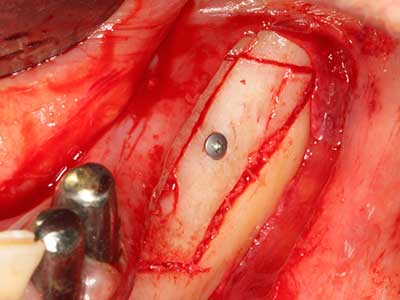

As shown in the past, basically any bone surgery procedure represents a possible indication for piezosurgery. Thus preparation of the mobile segment in distraction osteogenesis (Fig. 23-25) and sandwich osteotomy uses special attachments without endangering the blood supply to the crestal section, which is essential for the success of both techniques (Gonzalez-Garcia, Diniz-Freitas et al. 2008).

For removal of an implant, a vestibular bone cover that is replaced after removal of the implant screw can be prepared to retain the contour of the alveolar ridge.

There are additional applications in sinus surgery. Pathologies and foreign bodies can be removed from the sinus after concentric preparation of a generally trapezoid bone cover in the facial sinus wall. The bone cover is repositioned on conclusion of the intra-antral operation component and secured by wedging or adaptive sutures to prevent dislocation.